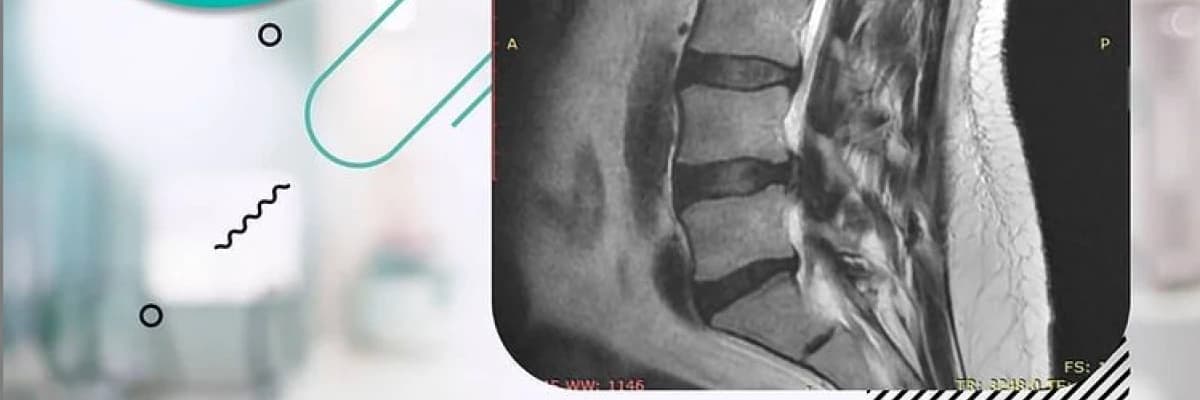

Omurgada, omurların arasında bulunan diskler herhangi bir nedenden dolayı hasar görürse, fıtık problemine yol açar. Fıtık, oturup kalkarken ve yatağa yatınca belden bacağa yayılan bir ağrı ile kendini gösterir. Fıtık fark edildiği anda tedavi edilmelidir. Zaman geçtikçe bölgedeki hasar artar ve tedavi zorlaşır.